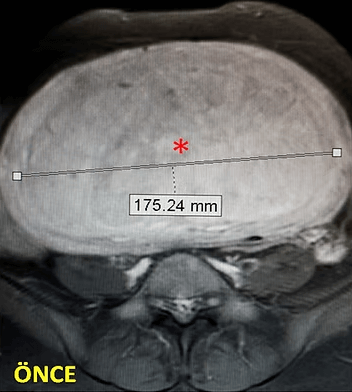

39 yaşında, kabızlık, gaz ve sık idrara çıkma şikayetleri var. Emar’da karını dolduran dev miyom (*) mevcut. Miyomektomi önerilmiş, ancak gerekirse rahimin alınabileceği söylenmiş. Embolizasyondan sonra dev miyom yanında bir başka küçük miyomun da öldüğü ve küçüldüğü izleniyor. 6 ay sonra hasta şikayeti kalmamıştır.